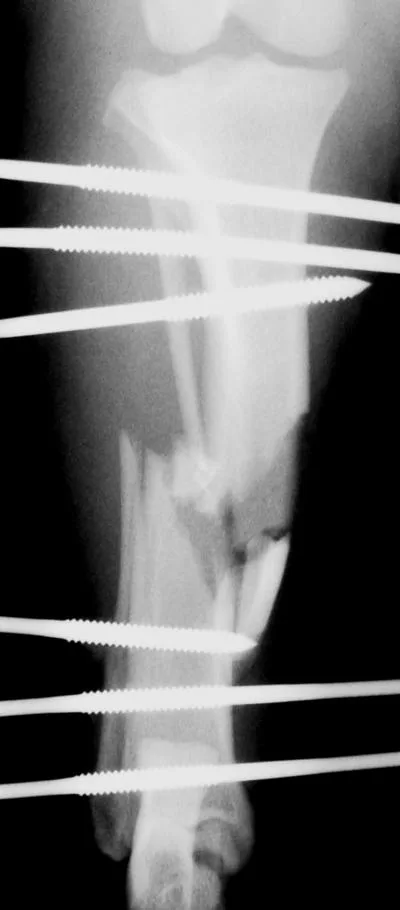

The interlocking-nail system (Innovative Animal Products, Rochester, MN) is another effective implant system for biologic management of comminuted fractures in dogs and cats.1 The interlocking nail is a modified Steinmann pin having transverse holes designed to accommodate screws or bolts. The addition of screws or bolts increases the ability of the pin to resist rotational and compressive forces at the fracture site (Figures 2A, B). This type of fixation is commonly used for stabilization of fractures of the femur and tibia in humans.

Interlocking nails are used in dogs and cats for repair of fractures of the humerus, femur, and tibia. The interlocking-nail system is less expensive than a bone-plate system but has similar biomechanical properties.8 Interlocking nails are easy to apply and are a good option for general practitioners who do not want to invest in a bone-plate system.

Fractures managed using interlocking nails and biologic technique develop extensive bridging callus and early return to function. A minimally invasive surgical approach (note the surgical skin staples) was made to this fracture to minimize disruption of the blood supply to the bone fragment. The fracture fragments quickly become incorporated in the callus if soft tissue attachments can be maintained.